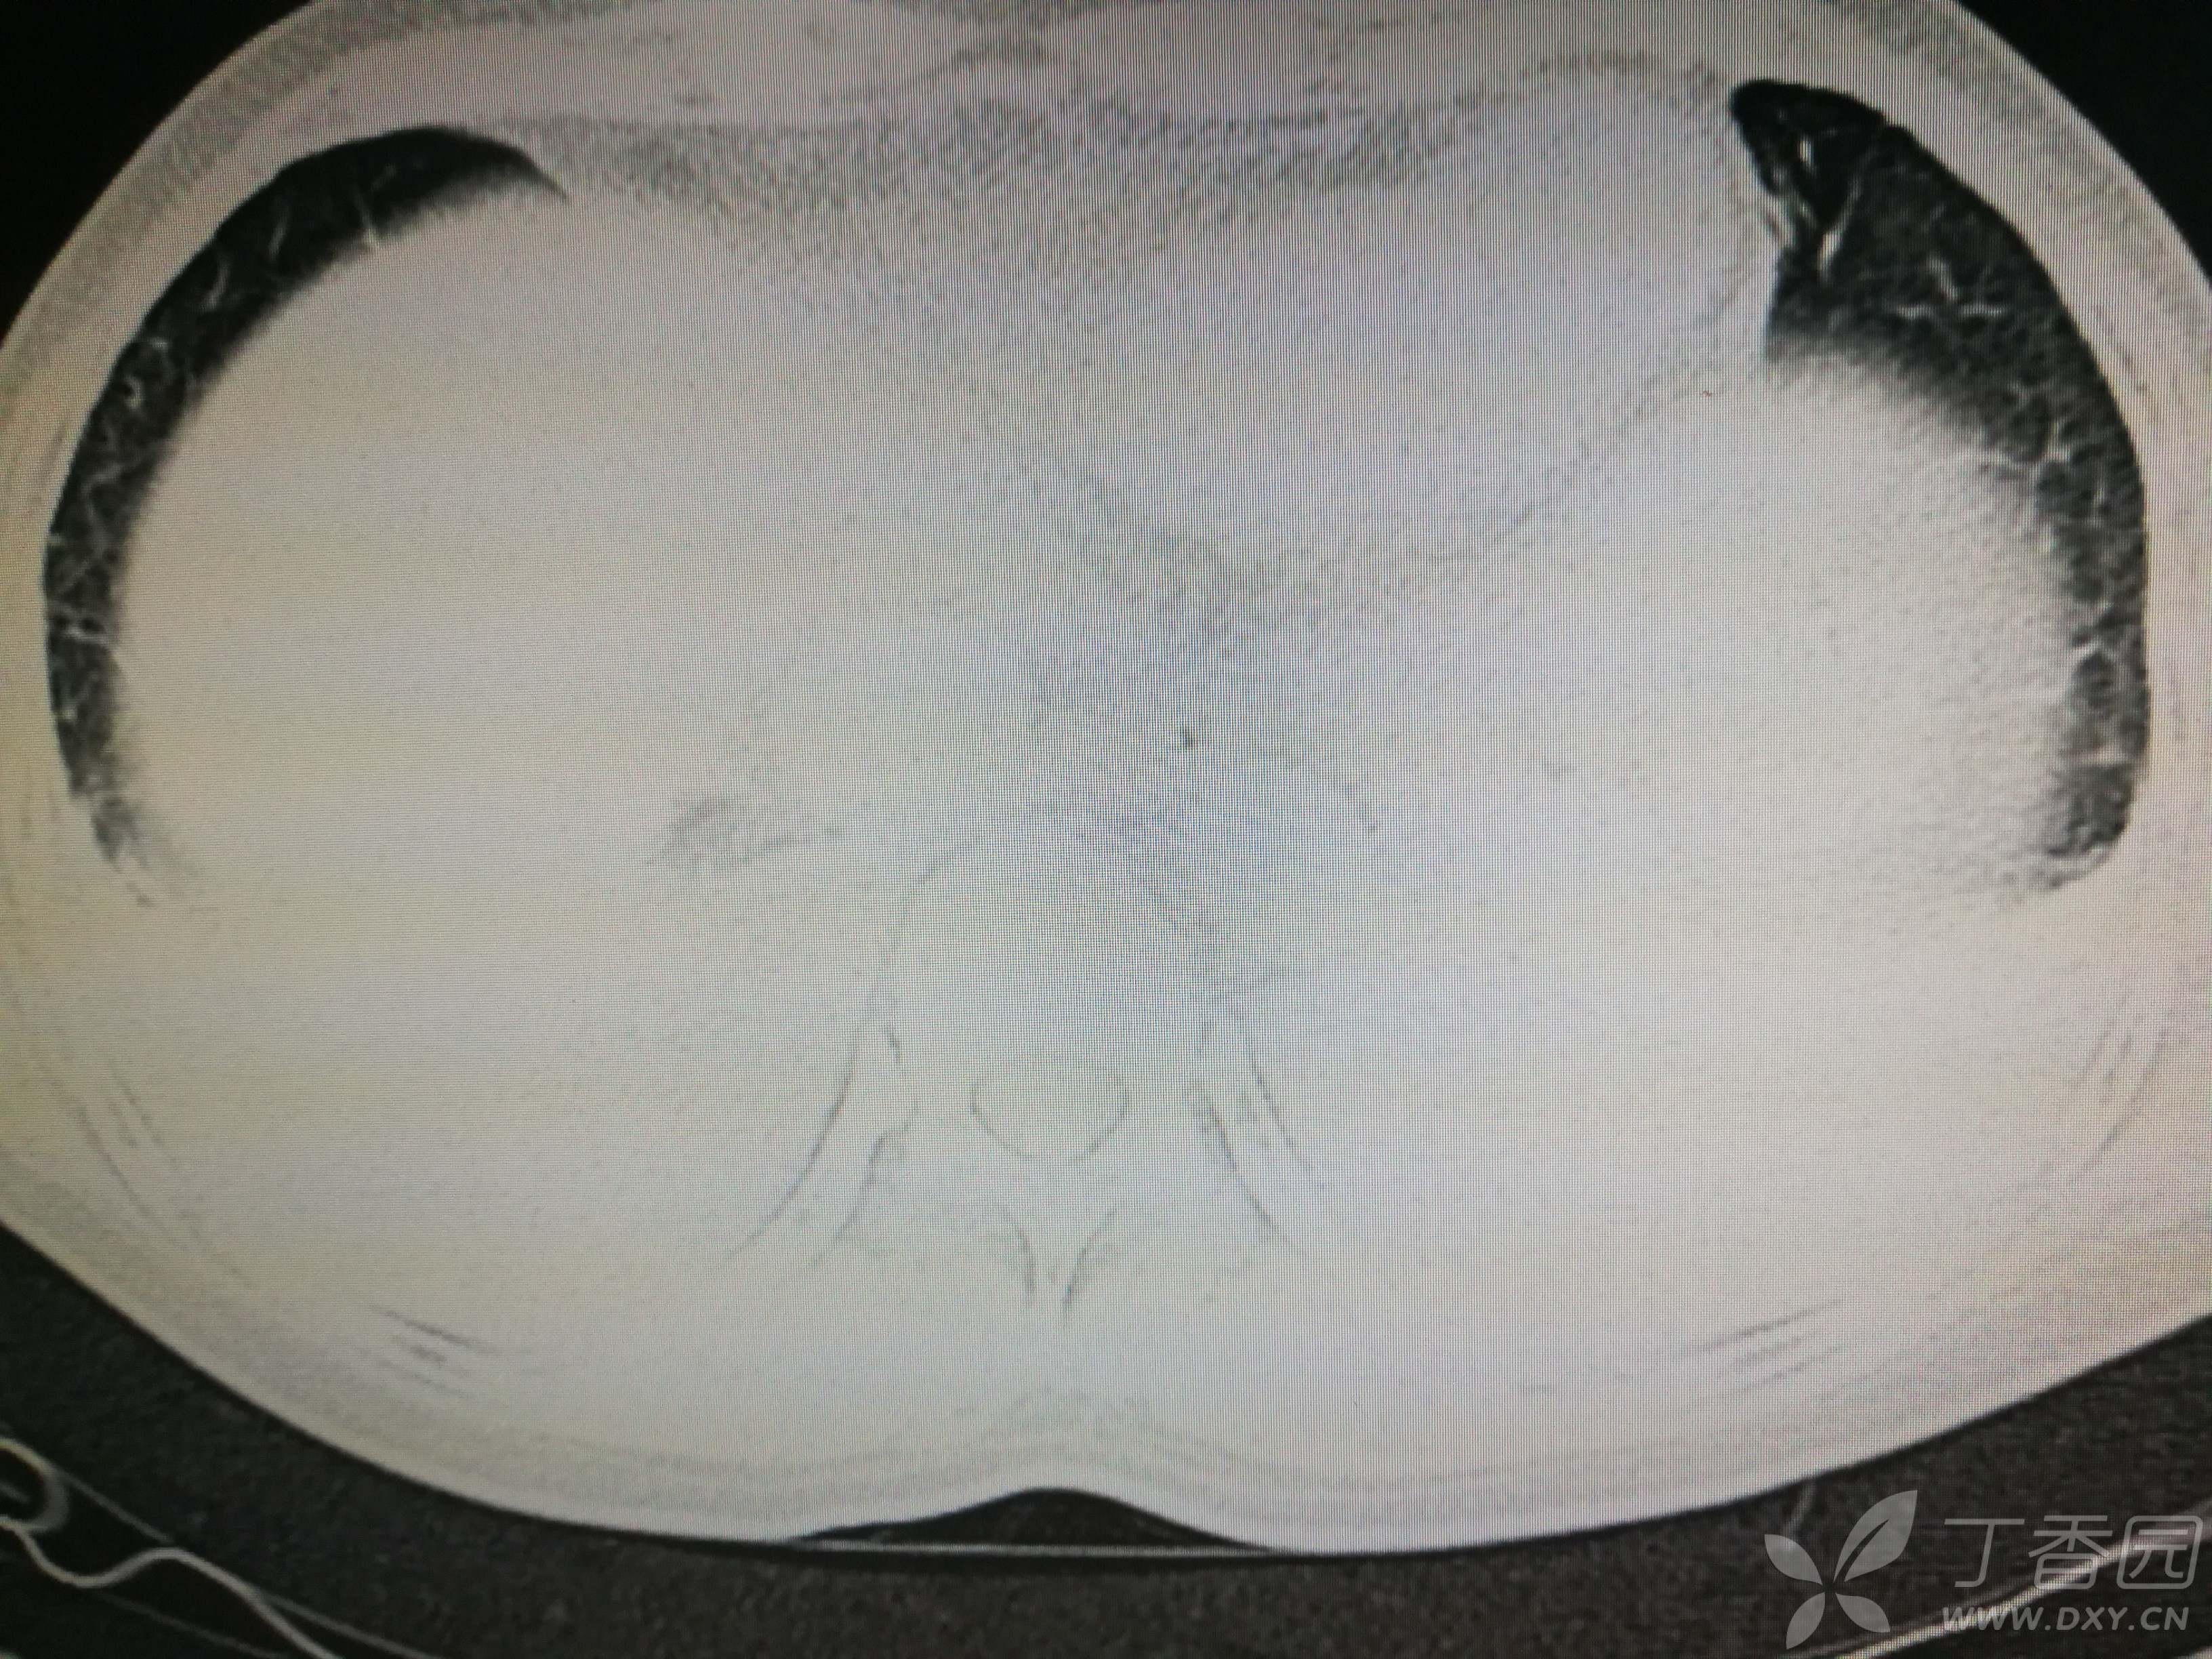

给予低分子肝素钙针抗凝、七叶皂苷钠针消肿及骨牵引固定等等治疗。入院后第四天行“左侧股骨下段骨折切开复位内固定术”(术前查双下肢彩超:双下肢深静脉血流通畅),手术顺利,术后予预防感染、预防血栓形成等治疗。术后患者无明显发热,生命体征平稳。术后第四天复查血常规:白细胞13.4×109/L,血红蛋白84g/L,血小板在正常范围。生化:白蛋白35.7g/L,余无明显异常。当天,患者开始出现轻度胸闷气急,可耐受。术后第五天患者胸闷气急加重,无胸痛,无背痛,无咯血,无意识障碍,无头晕头痛,无恶心呕吐等,急查凝血功能:纤维蛋白原降解产物12mg/L,D二聚体4000ug/L,余无明显异常。查动脉血气分析:pH7.52,氧分压62mmHg,二氧化碳分压30mmHg,碱剩余1.8mmol/L,乳酸1.0mm/L,血红蛋白86g/L。查胸部CT见下(先视频后图片):